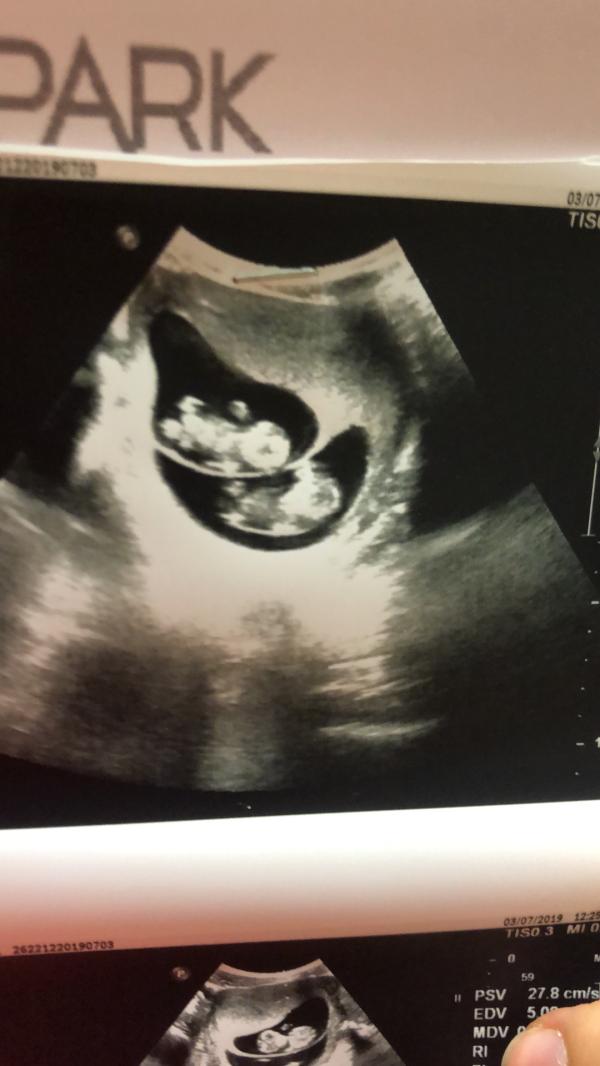

На 11-той недели беременности я уже приехала в Стамбул и пошла на УЗИ, когда я чётко увидела двоих у себя в животе я не могла поверить в это. Жаль мужа не было рядом(( Сказать что я была в шоке это ничего не сказать. У нас в роду ни у кого нет двойни.